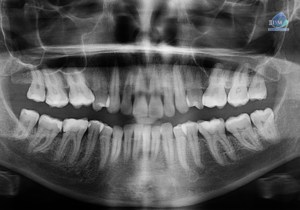

Paciente femenina de 38 años de edad acude al instituto de Diagnóstico maxilofacial – IDM (surco) para evaluación imagenológica general. En la radiografía panorámica (Figura